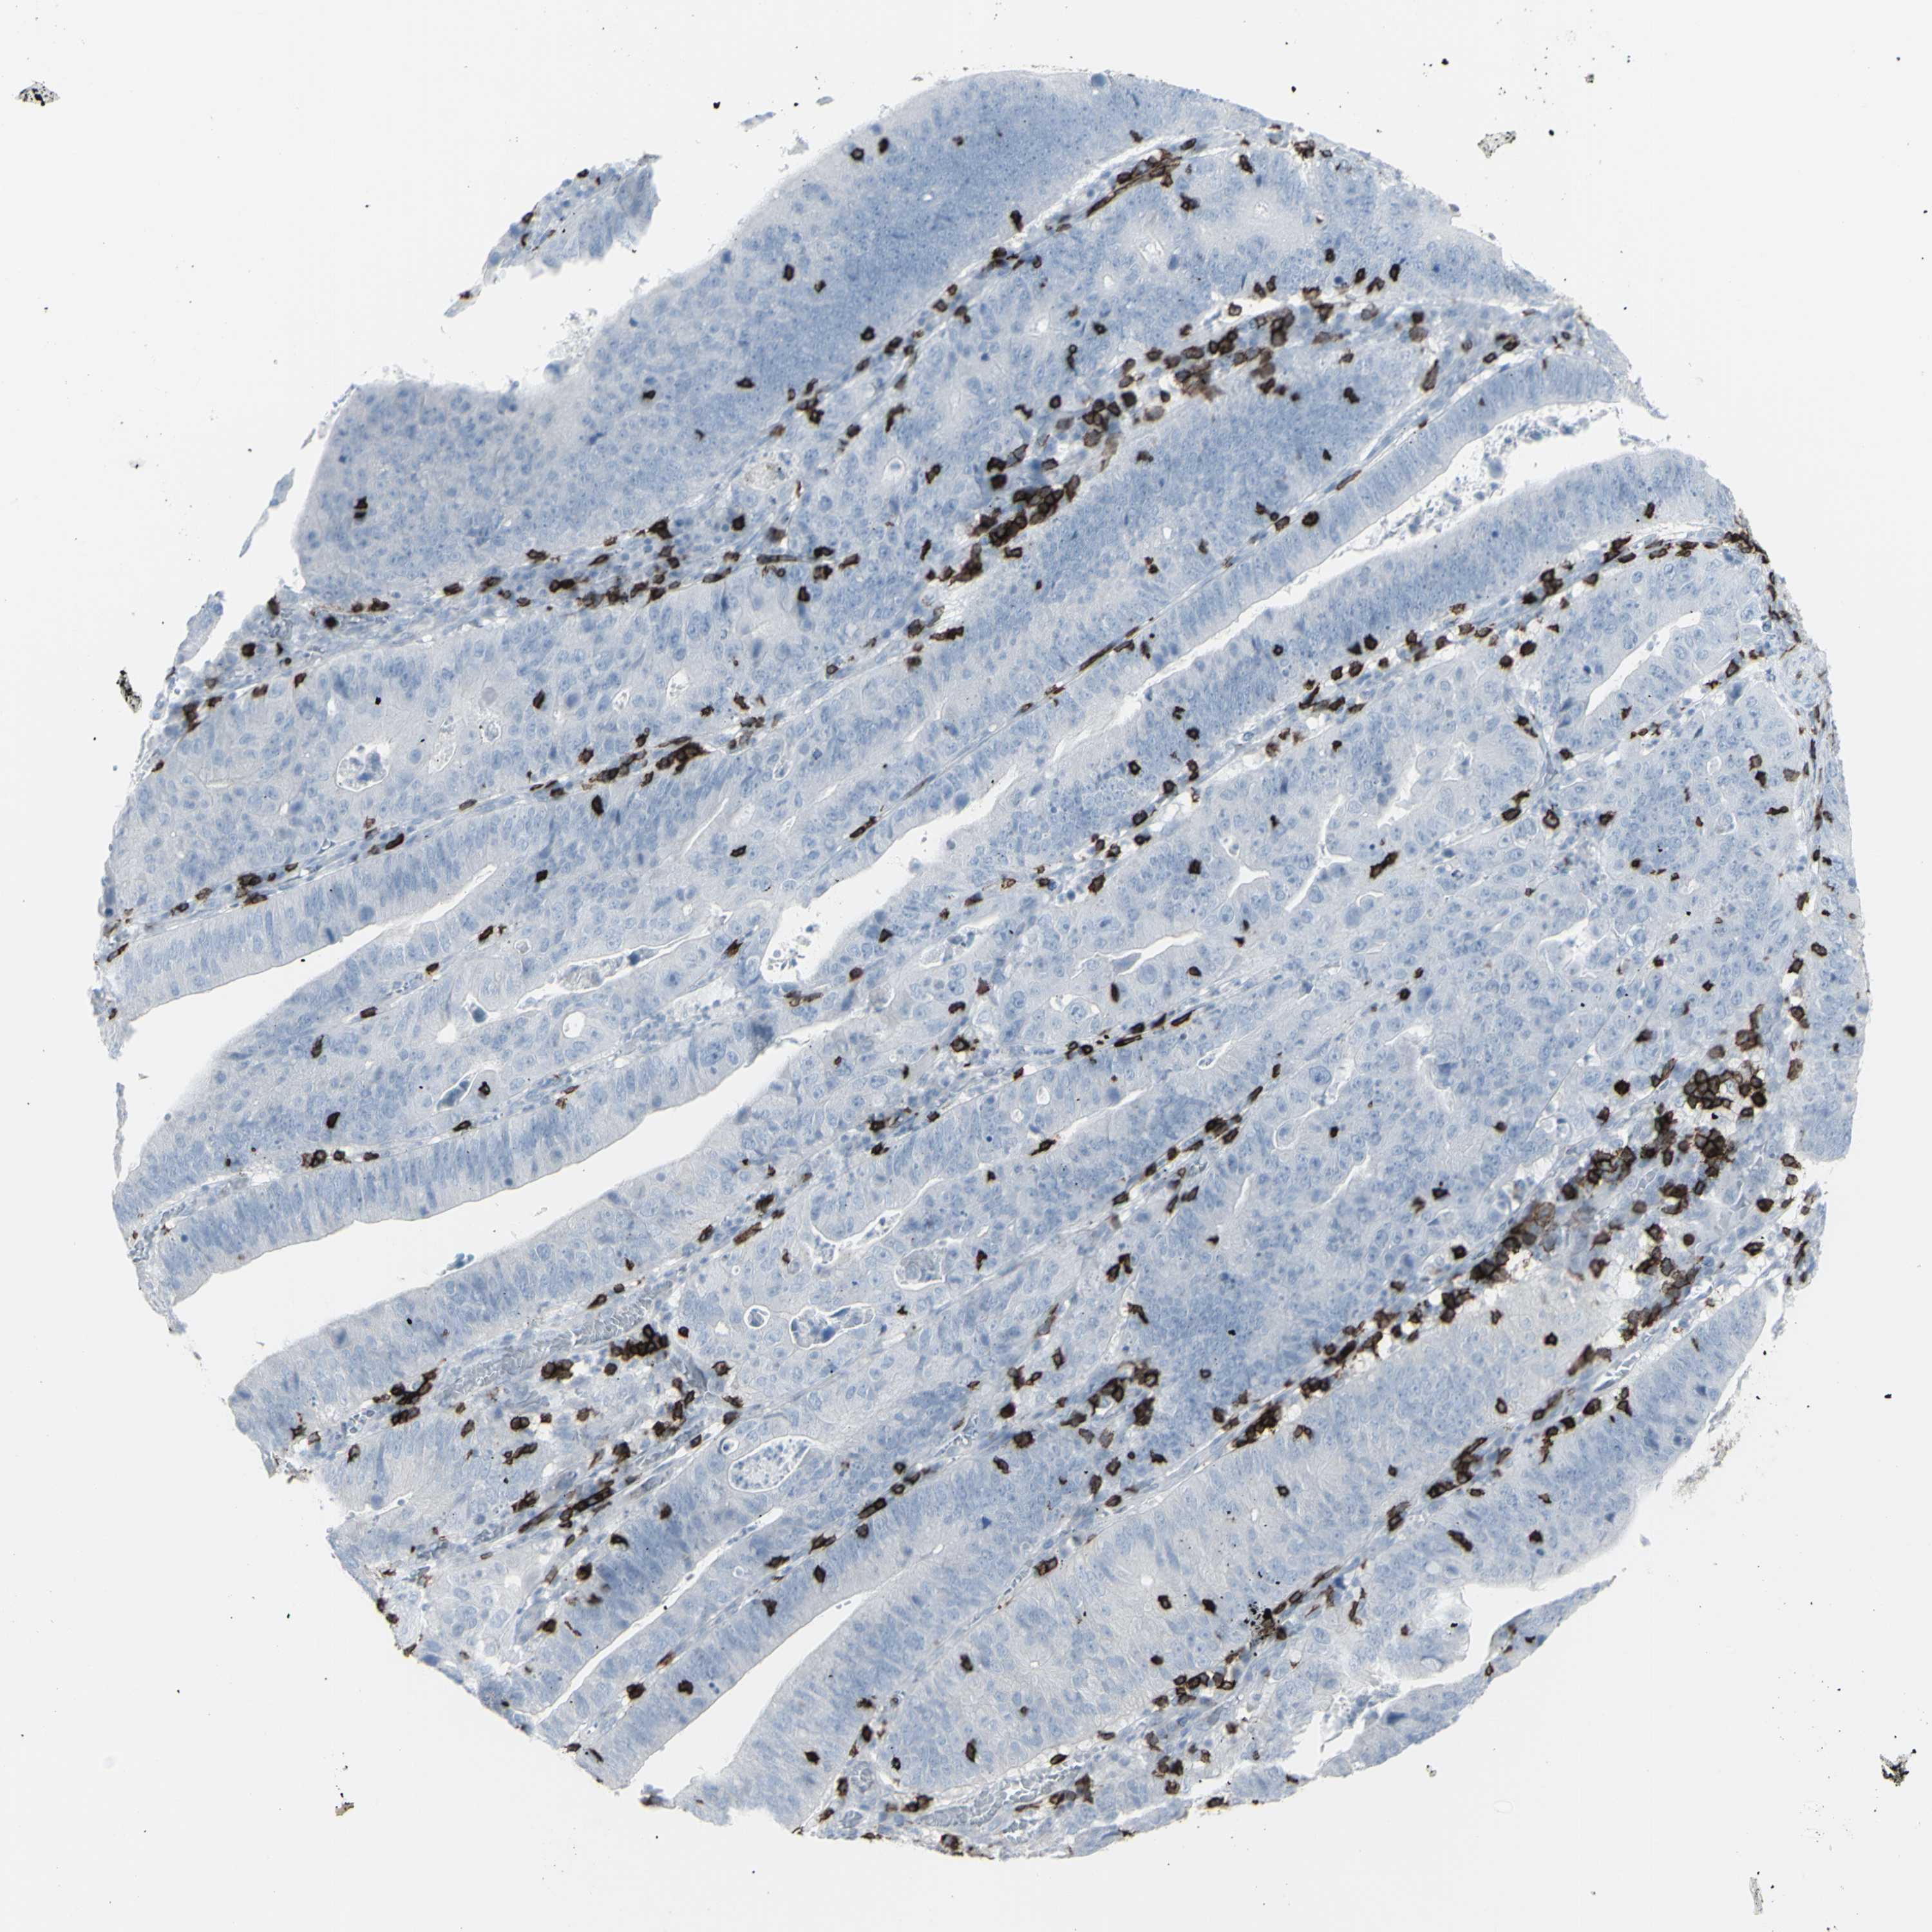

STOMACH CANCER - Protein expressioni

A mouse-over function shows sample information and annotation data. Click on an image to view it in a full screen mode. Samples can be filtered based on level of antibody staining by selecting one or several of the following categories: high, medium, low and not detected. The assay and annotation is described here.

Note that samples used for immunohistochemistry by the Human Protein Atlas do not correspond to samples in the TCGA dataset.

Antibody stainingi

Antibody staining in the annotated cell types in the current human tissue is reported as not detected, low, medium, or high, based on conventional immunohistochemistry profiling in selected tissues. This score is based on the combination of the staining intensity and fraction of stained cells.

Each image is clickable and will lead to virtual microscopy that enables deeper exploration of all samples and also displays staining intensity scores, fraction scores and subcellular localization as well as patient and tissue information for each sample.

Antibody HPA008750

Antibody CAB004651

Staining

High

Medium

Low

Not detected

Intensity

Strong

Moderate

Weak

Negative

Quantity

>75%

75%-25%

<25%

None

Location

Nuclear

Cytoplasmic/membranous

Cytoplasmic/membranous,nuclear

Adenocarcinoma, NOS

Adenocarcinoma, High grade